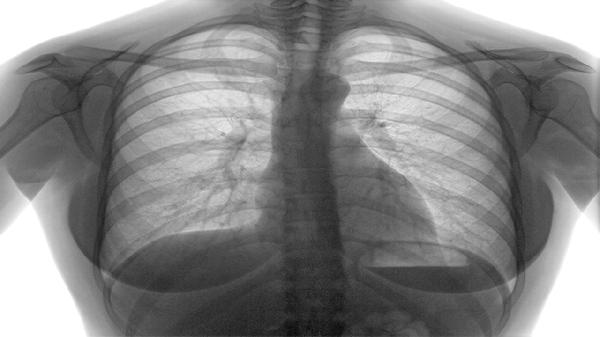

1、手术是甲癌淋巴转移的首选治疗方式,包括甲状腺全切除术、颈部淋巴结清扫术和中央区淋巴结清扫术。手术能直接切除病灶,减少肿瘤负荷,为后续治疗创造条件。术后需定期复查,监测甲状腺功能和肿瘤标志物。

2、放疗在甲癌淋巴转移中起到重要作用,包括外照射放疗和放射性碘治疗。外照射放疗通过高能射线杀灭癌细胞,放射性碘治疗利用甲状腺癌细胞对碘的摄取能力,选择性地破坏癌细胞。放疗需根据病情制定个性化方案,注意保护周围正常组织。